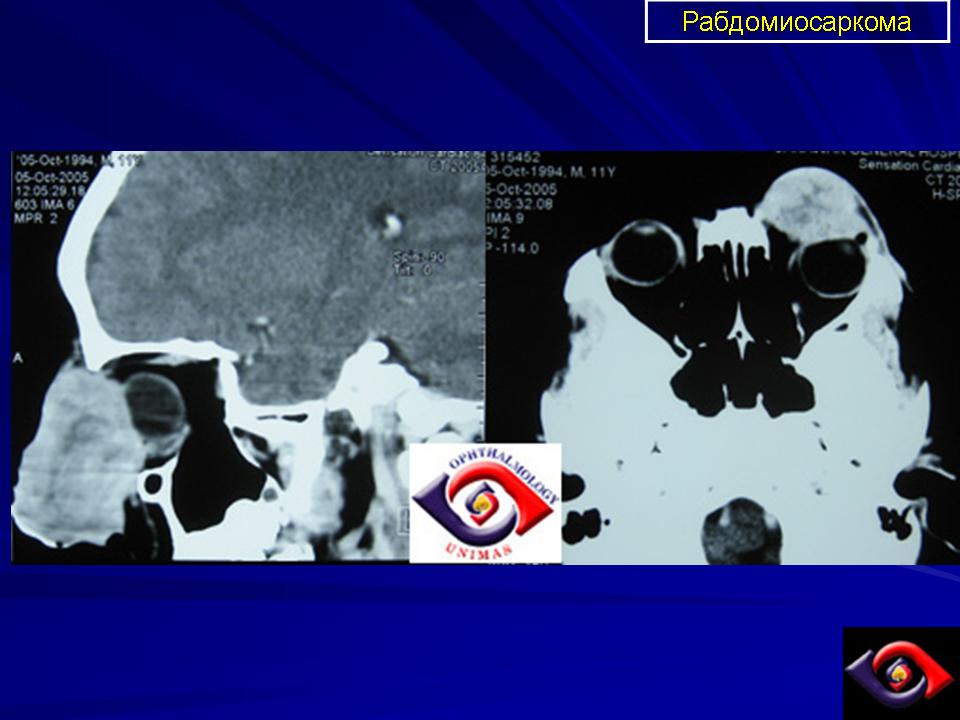

Рабдомиосаркома — чрезвычайно агрессивная опухоль орбиты, является наиболее частой причиной злокачественного роста в орбите у детей. Мальчики болеют почти в 2 раза чаще. Источником роста рабдомиосаркомы являются клетки скелетных мышц. Выделены три типа опухоли: эмбриональный, альвеолярный и плеоморфный, или дифференцированный. Последний тип встречается редко. У детей до 5 лет чаще развивается эмбриональный тип опухоли, после 5 лет — альвеолярный. Как правило, рабдомиосаркома состоит из элементов нескольких типов (смешанный вариант). Точный диагноз можно установить только на основании результатов электронной микроскопии.

Излюбленная локализация опухоли — верхневнутренний квадрант орбиты, поэтому в процесс рано вовлекаются мышца, поднимающая верхнее веко, и верхняя прямая мышца. Птоз, ограничение движений глаза, смещение его книзу и книзу кнутри — это первые признаки, на которые обращают внимание как сами больные, так и окружающие лица. У детей экзофтальм или смещение глаза при локализации опухоли в переднем отделе орбиты развивается в течение нескольких недель (рис. 20.23, а). У взрослых опухоль растет медленнее, в течение нескольких месяцев. Быстрое увеличение экзофтальма сопровождается появлением застойных изменений в эписклеральных венах, глазная щель полностью не смыкается, отмечаются инфильтраты на роговице и ее изъязвление. На глазном дне — застойный диск зрительного нерва. Первично развиваясь вблизи верхневнутренней стенки орбиты, опухоль быстро разрушает прилежащую тонкую костную стенку, прорастает в полость носа, вызывая носовые кровотечения. Ультразвуковое сканирование, компьютерная томография, термография и тонкоигольная аспирационная биопсия — это оптимальный диагностический комплекс инструментальных методов исследования при рабдомиосаркоме (рис. 20.23, б). Лечение комбинированное. Протокол лечения предусматривает предварительное проведение полихимиотерапии в течение 2 нед, после чего проводят наружное облучение орбиты. После комбинированного лечения более 3 лет живут 71 % больных.